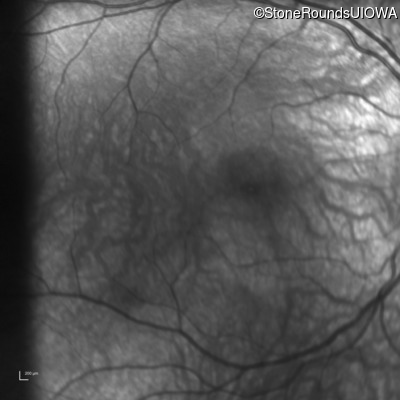

Infrared Fundus Photograph - Right - 10/125

Exemplar